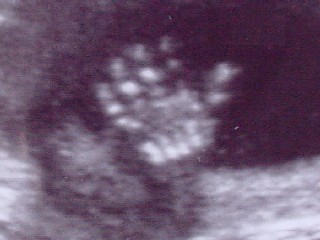

* Talk to the Hand *

This is a cropped out shot of a friend's ultrasound, as the fetus seems to be displaying a bit of resentment to having it's picture taken.

Now, as many of you know, I don't usually post images that I don't take myself. But I did scan and crop the ultrasound images for my friend so that she could email them to all her friends and family and share the beginning of this new little human.